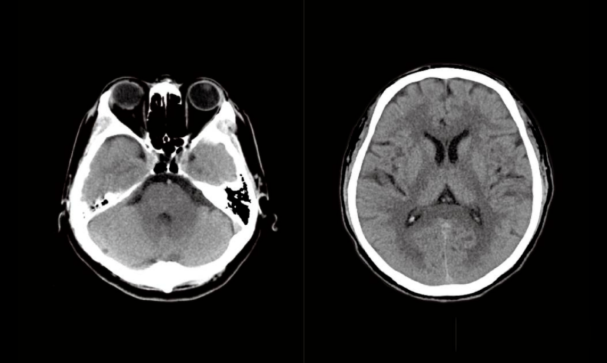

7、颅脑CT检查:

是一种检查方便,无痛苦,无创伤且迅速安全的检查方法,它能清楚的显示颅脑不同横断面的解剖关系和具体的脑组织结构。因而大大提高了病变的检出率和诊断的准确性。